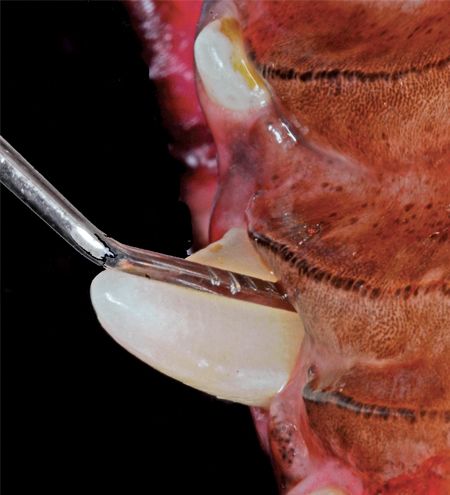

Palatal pocket therapy is indicated in cases in which there is more than 25 percent attachment loss on the palatal aspect of one or both maxillary canine teeth and the periodontal probe does not enter the nasal cavity (Photo 9). If untreated, the pocket might progress until it penetrates the nasal cavity, creating an oronasal fistula.

Photo 9: A 7-mm palatal pocket.